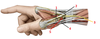

1? 2?

1: Greater tubercule of humerus

2: Coracoid process of scapula

3?

Clavicle

4? 5?

4: Spinous process of scapula

5: Acromion of scapula

6?

Inferior angle of scapula

7? 8?

7: Scapula

8: Humerus

9?

Lesser tubercle of humerus